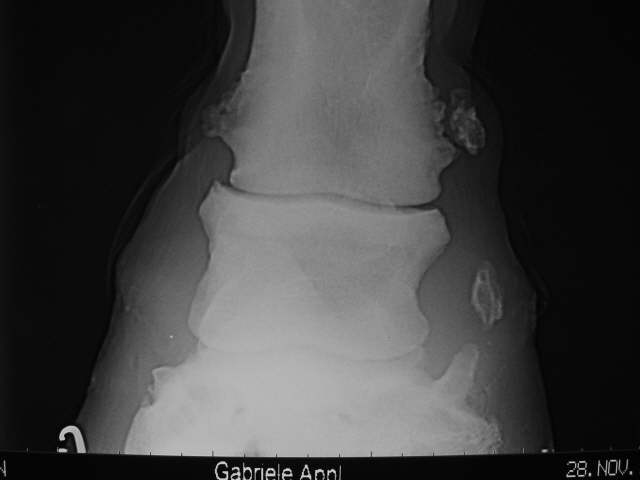

Isolierte Verknöcherung im Hufknorpel rechts und hochgradige Krongelenksarthrose mit Mineralisation